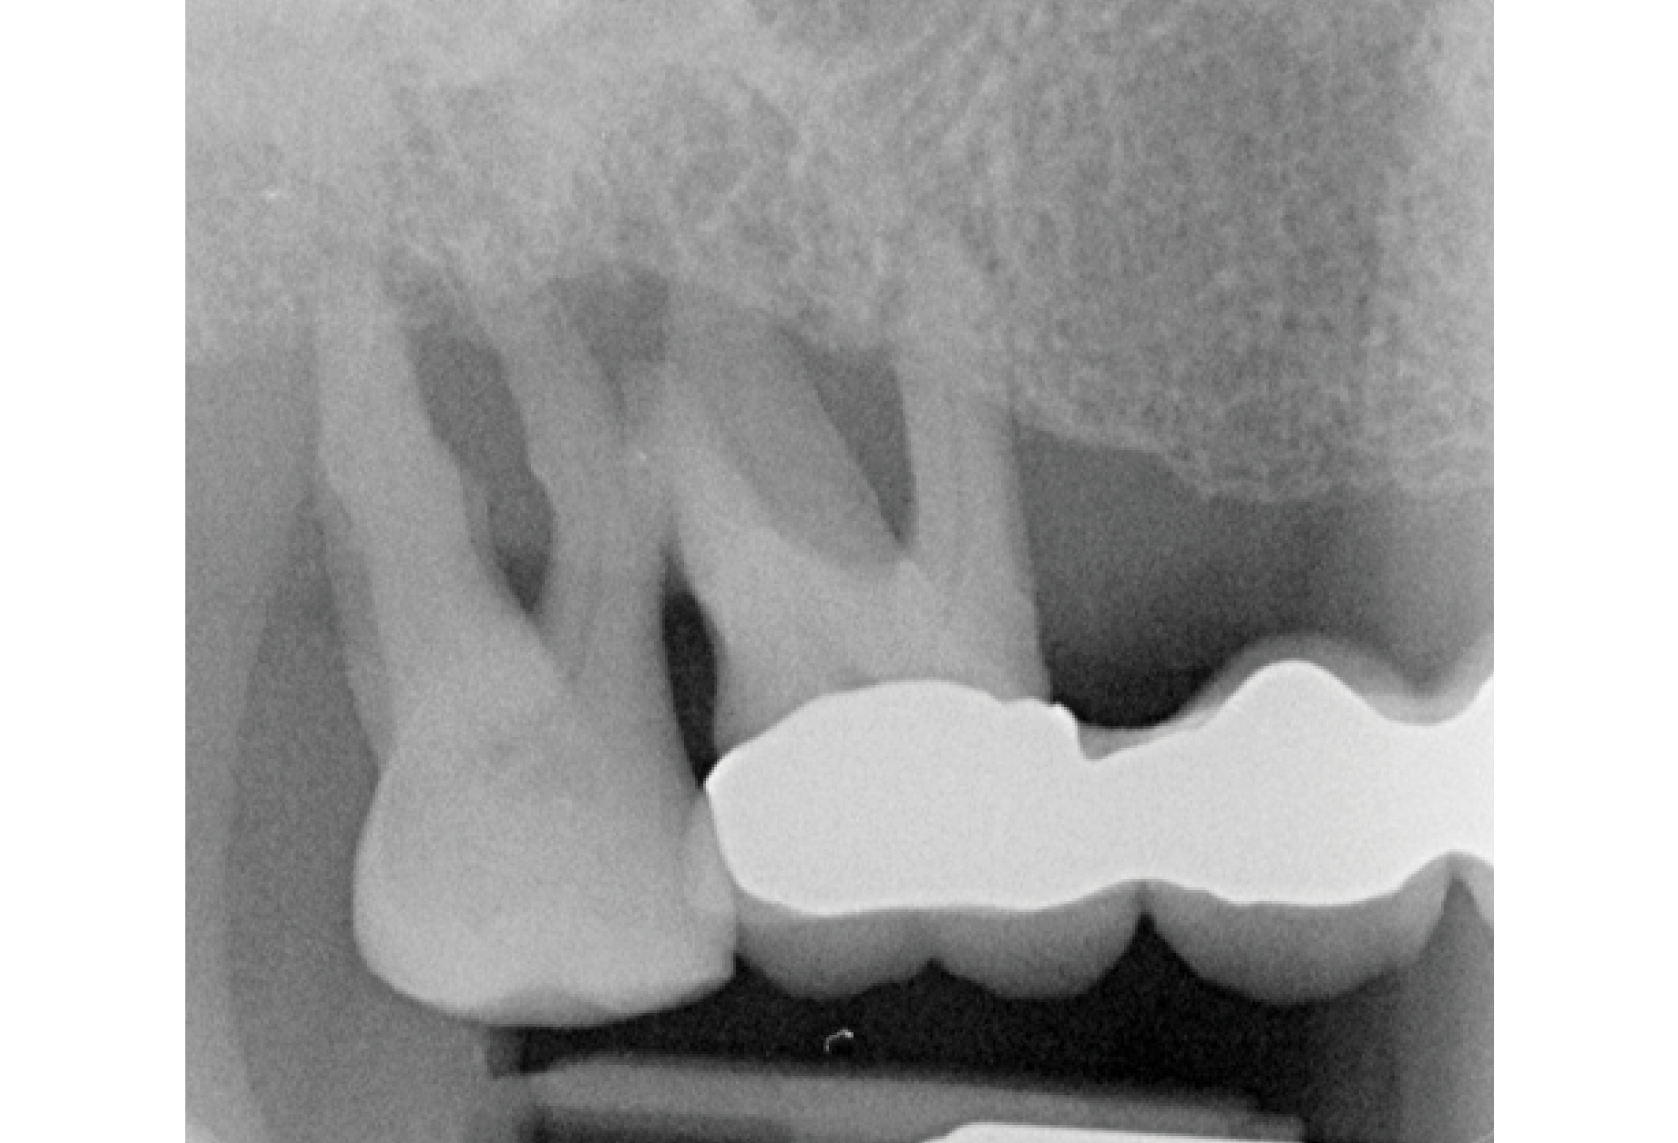

The periodontal dilemma:

When to save, when to let go?

When to save, when to let go?

Course Topic

Periodontics

● Understanding the literature of prognosticating periodontally compromised dentition

● What are some of the factors periodontists assess to diagnose the prognosis of the tooth?

● Additional considerations before deciding whether save or remove teeth